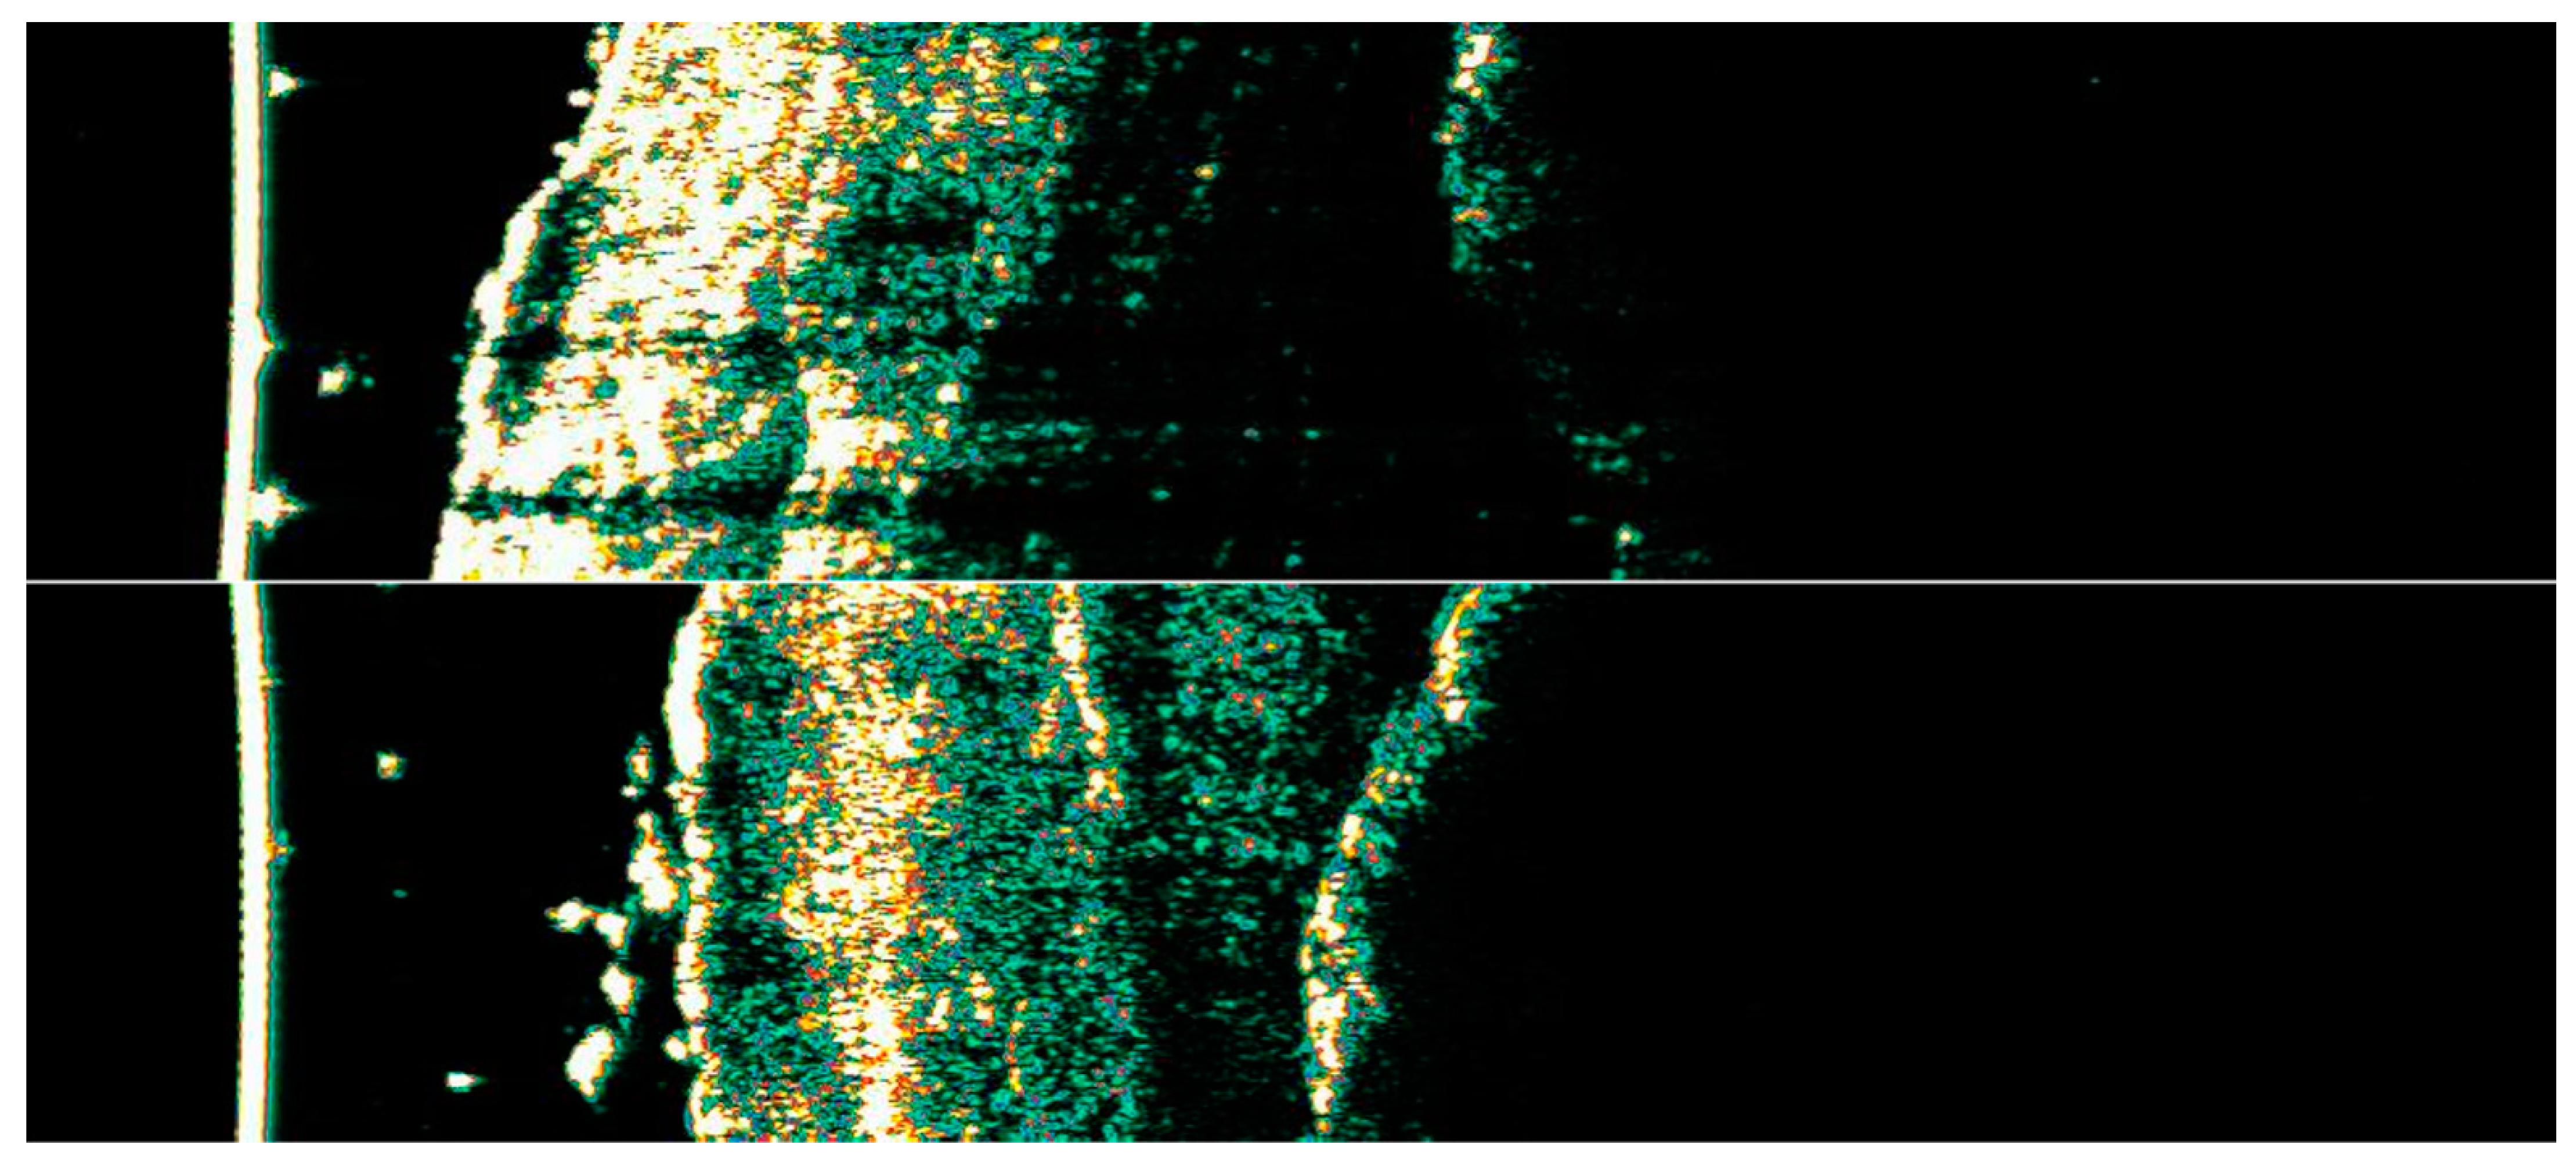

2.2. Dermoscopic Evaluation

3.1. Clinical and Dermoscopic Involution of HIFU-Treated Basal Cell Carcinoma